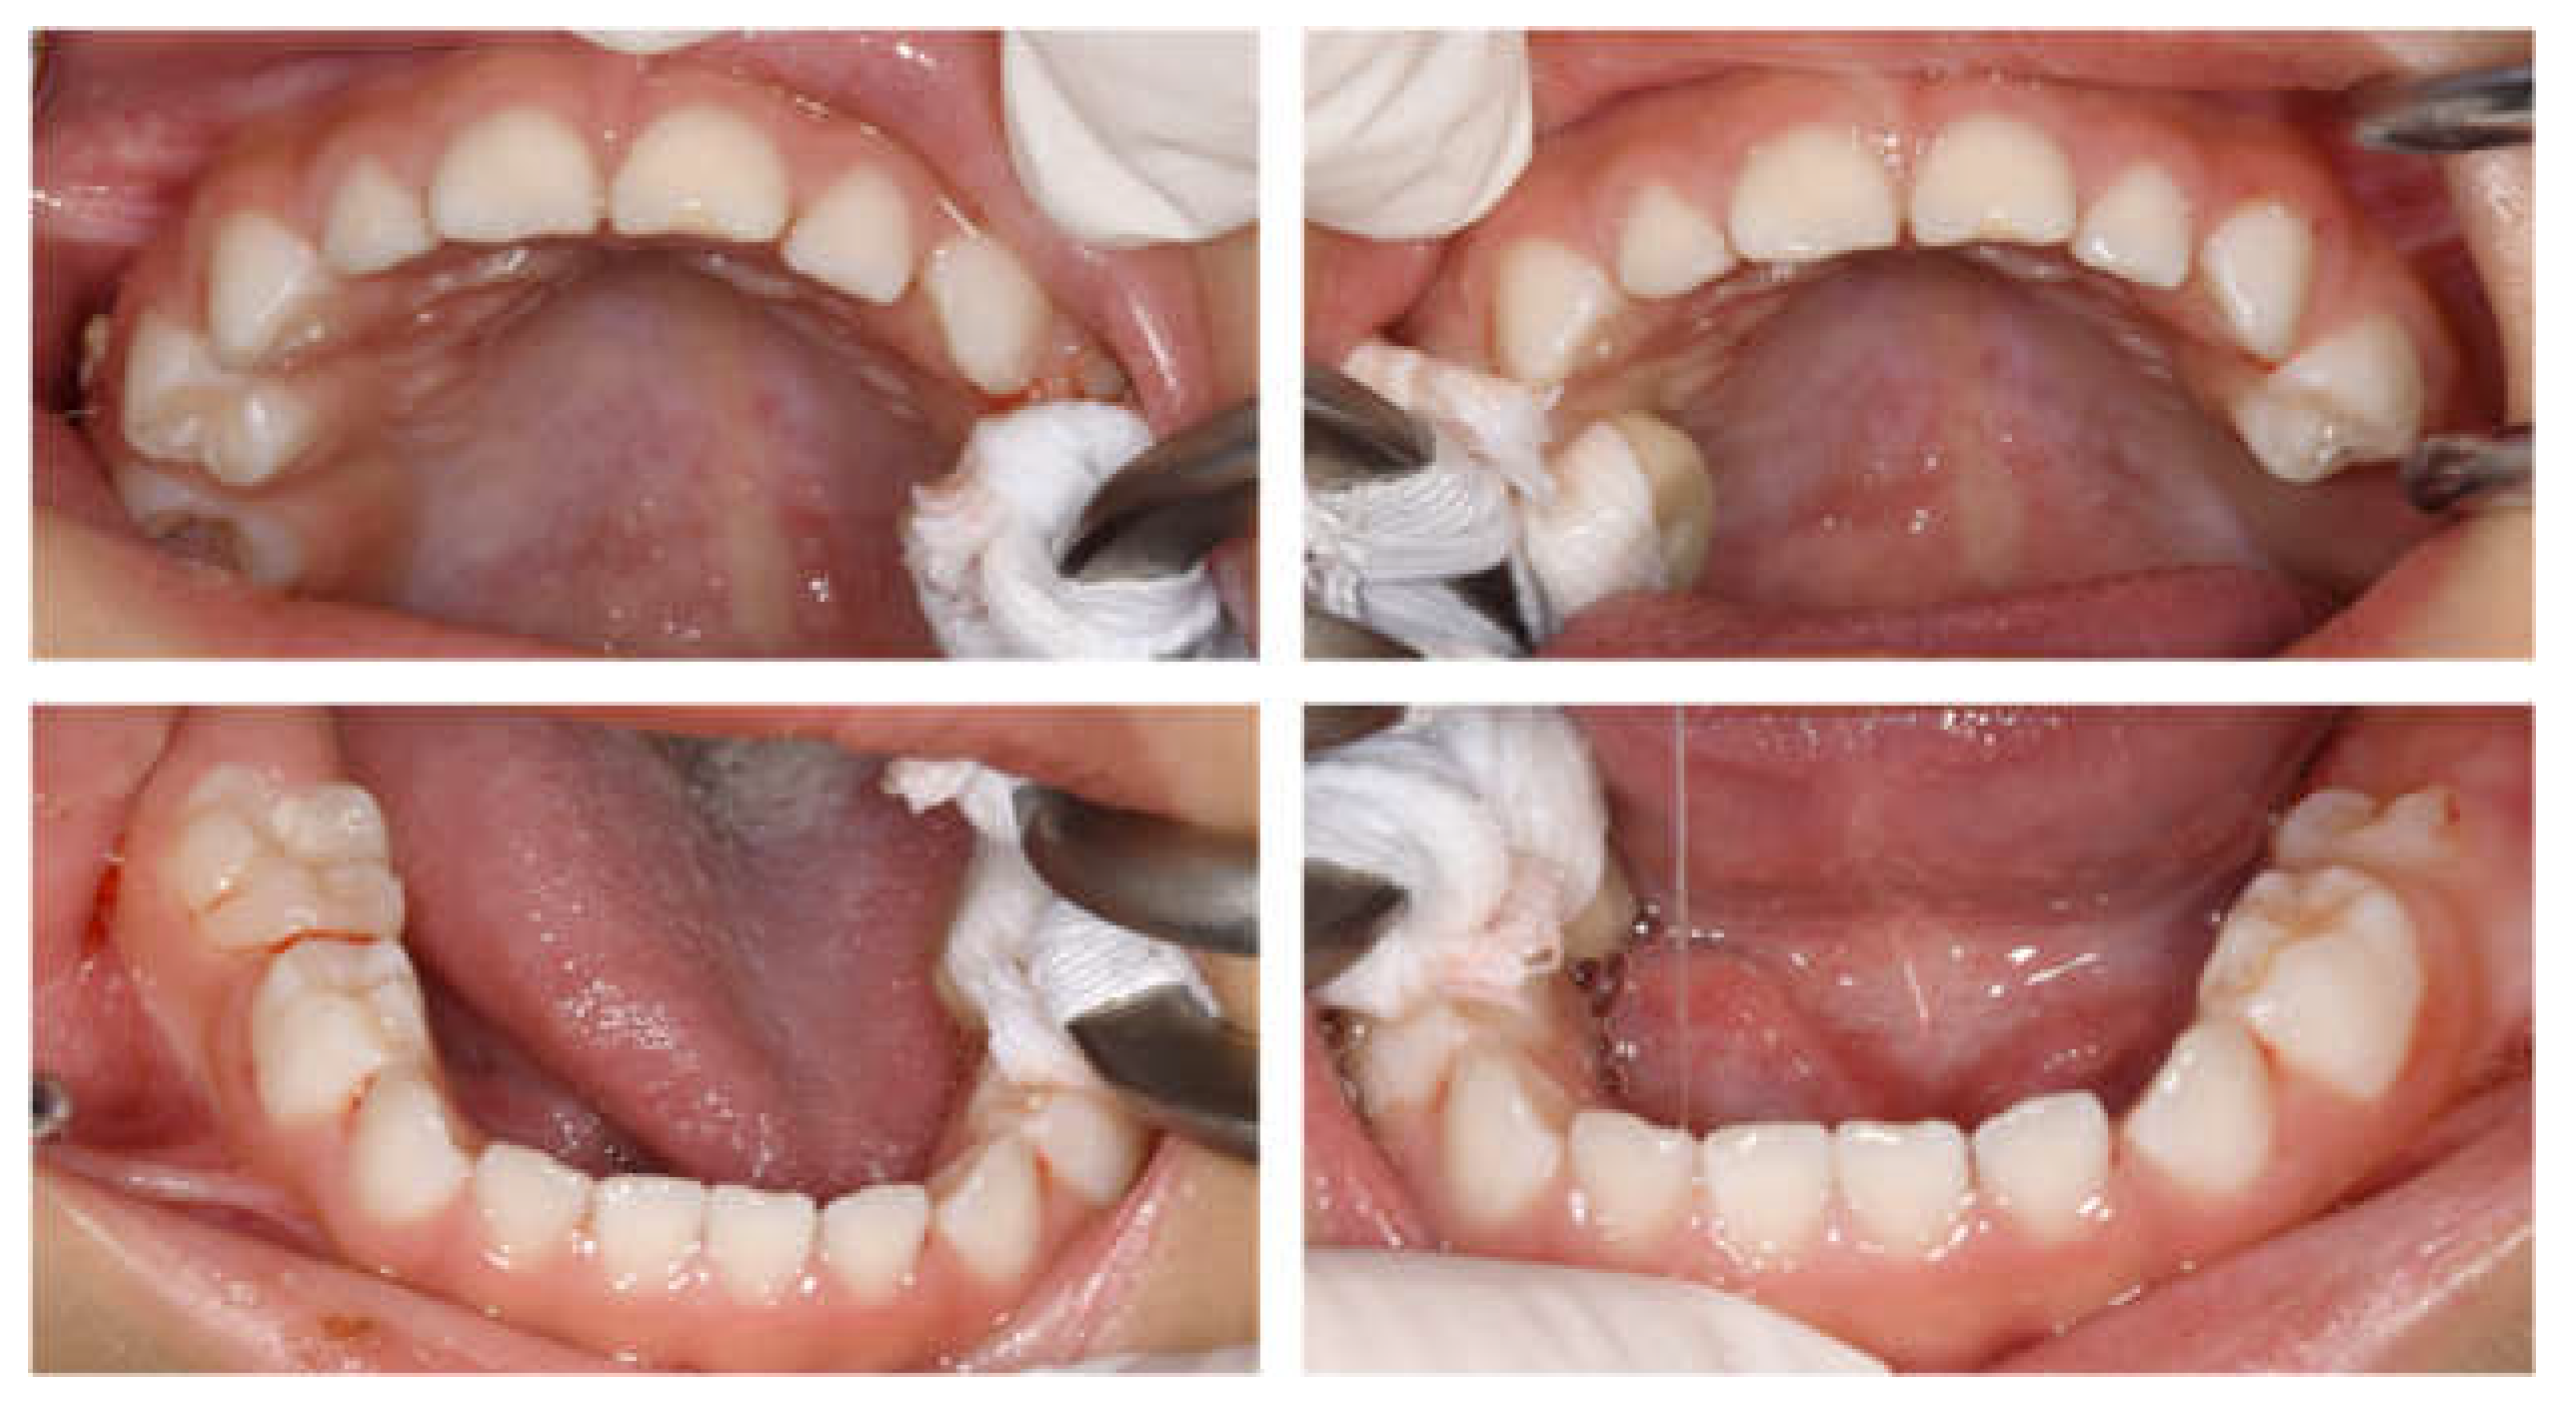

| Tooth | Diagnosis | Final Restoration |

|---|---|---|

| Maxilla | ||

| 51 | C2 | Resin-based composite crown |

| 52 | C2 | Resin-based composite crown |

| 53 | C2 | Resin filling |

| 54 | C2 | Preformed stainless-steel crown |

| 55 | C2 | Preformed stainless-steel crown |

| 61 | C2 | Resin-based composite crown |

| 62 | C2 | Resin-based composite crown |

| 63 | C2 | Resin filling |

| 64 | C2 | Preformed stainless-steel crown |

| 65 | C2 | Preformed stainless-steel crown |

| Mandible | ||

| 71 | C2 | No treatment |

| 72 | C2 | Resin filling |

| 73 | C2 | Resin filling |

| 74 | C2 | Preformed stainless-steel crown |

| 75 | C2 | Preformed stainless-steel crown |

| 81 | C2 | No treatment |

| 82 | C2 | Resin filling |

| 83 | C2 | Resin filling |

| 84 | C2 | Preformed stainless-steel crown |

| 85 | C2 | Preformed stainless-steel crown |